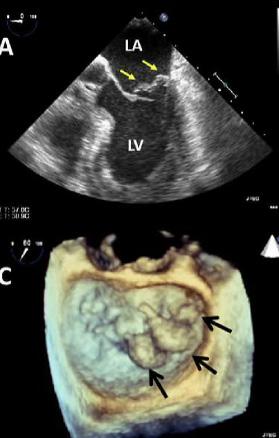

Imagens do ecocardiograma mostrando a válvula mitral, permitindo a avaliação de suas características e função. É através de imagens como essas que o médico ecocardiografista consegue avaliar a doença reumática da válvula mitral, prolapsos, e dificuldades de abertura ou fechamento da válvula.